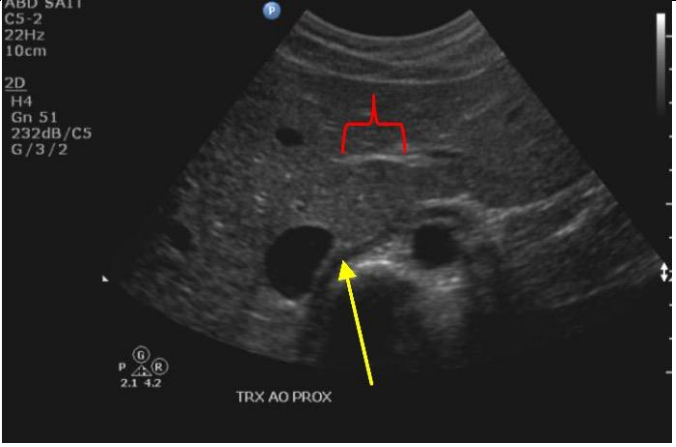

16

Q

Which ligament is the red bracket indicating? And label the yellow arrow

A

Red bracket: Ligamentum venosum

Yellow arrow: Right crux of the diaphragm